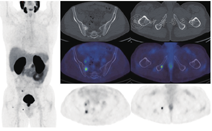

4.68Ga-PSMA PET/CT。由于PSMA显像剂能显示骨髓活性,所以对表达PSMA的骨转移而言,68Ga-PSMA显像的优势比18F-胆碱更明显(图5)[22]。一些研究表明,对前列腺癌骨转移,68Ga-PSMA PET/CT显像比骨显像具有更高的灵敏度[57,58,59],其与18F-fluoride PET/CT显像灵敏度相近,甚至更优[57,60]。这些研究结果表明,如果已进行PSMA PET/CT显像,则大多数前腺癌患者不需要再行其他骨特异性显像[58,59,60]。然而,另有一项研究表明,在计划进行放疗的晚期前列腺癌患者中,PSMA PET/CT显像对骨转移检出的灵敏度较低[61]。这些患者以前接受过常规治疗,上述18F-胆碱与18F-fluoride显像比较时所描述的肿瘤异质性反应[62]使得某些骨转移瘤的肿瘤细胞处于代谢静止状态(PSMA显像阴性),但仍具有持续的成骨细胞修复活性(18F-fluoride显像阳性)。

68Ga-PSMA显像假阳性较少见,但Paget病有68Ga-PSMA显像剂摄取[63]。虽然目前关于PSMA PET显像用于监测前列腺癌患者骨转移治疗反应的数据不足,但有报道雄激素剥夺治疗后骨转移灶可出现代谢闪烁现象,需引起注意[64]。